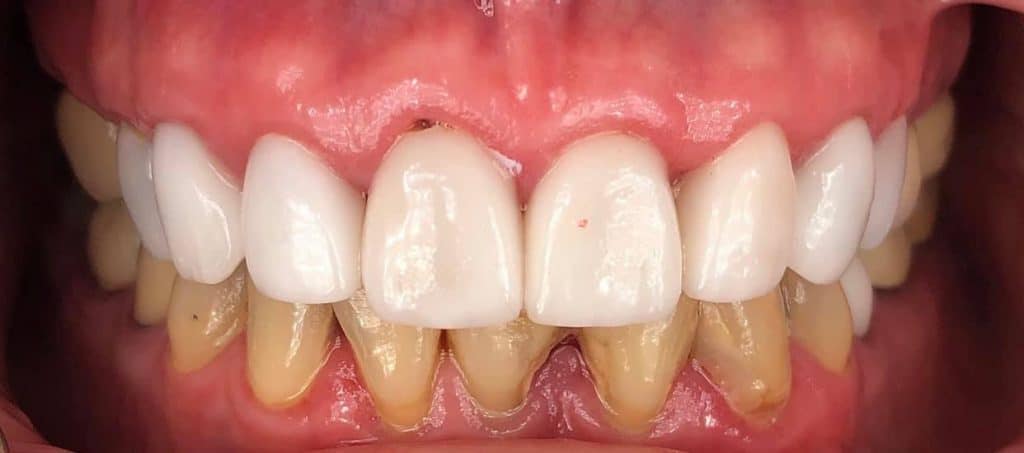

The final bridge was constructed in monlithic zirconia.

-Immediate load temp upper